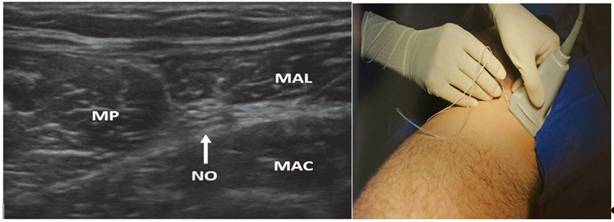

Bloqueo del nervio obturador, ecoguiado con sonda recta de alta frecuencia y aguja ecorrefringente de 100 mm (Pajunk®), se administró 5 ml de bupivacaína 0,5 % más adrenalina 1/200000, en sus 2 rama (superficial y profunda), las cuales se visualizaron como una estructura plana e hiperecoica entre el músculo pectíneo y los músculos aductores (figura 4).

A izquierda, se muestra la imagen ecográfica del Nervio Obturador (NO). MP-Musculo Pectíneo, MAL- Musculo Aductor largo, MAC-Musculo Aductor Corto. A derecha, la posición de la sonda ecográfica para obtener la imagen